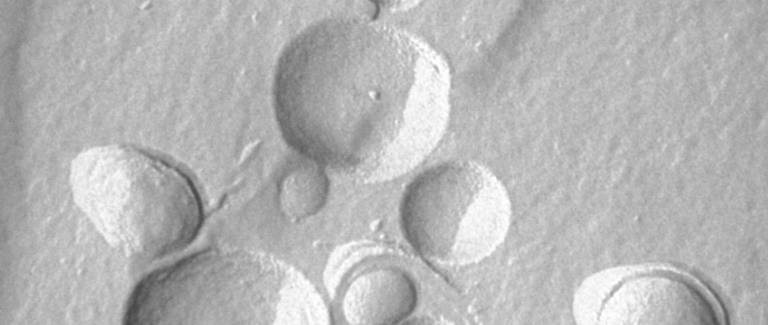

Ihre wissenschaftliche Arbeit in Diagnostik und Wirkstoff-Entwicklung wird durch unsere elektronenmikroskopischen Untersuchungen und Bilddokumentationen im wahrsten Sinne des Wortes anschaulich erklärt und deutlich beschleunigt.

Microscopy Services setzt das patentierte Analyseverfahren Lipbarvis® (Lipid Barrier Visualisation, LBV) ein, um die epidermale Hautbarriere direkt ohne invasive Probenahmen untersuchen zu können.